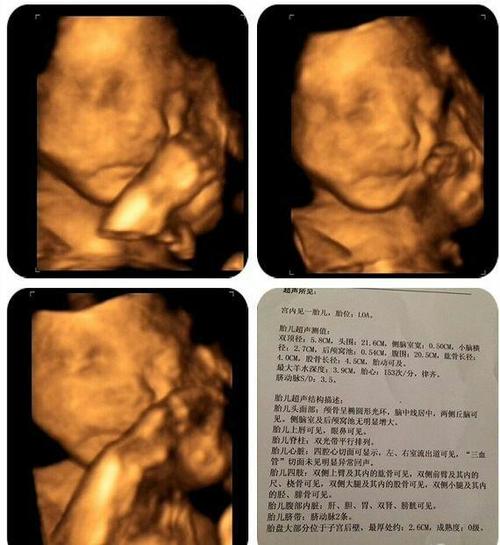

四维兔唇图片,轻度兔唇四维彩超图片

四维图片唇裂

四维没通过胎儿上唇发现暗带不知道怎么回

轻度兔唇四维彩超图片

四维彩超兔唇照片

四维彩超轻微兔唇图片

四维兔唇图片是什么样

四维彩超图片

胎儿四维照片